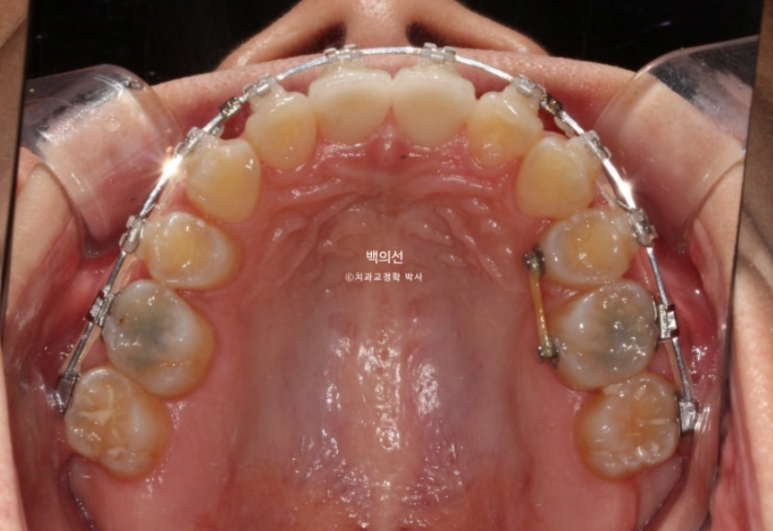

치료기간이 이미 2년 10개월이 된만큼 교정치료 마무리 단계입니다.

그런데 엑스레이상 치아 뿌리의 평행이 맞지 않는 부분들이 보입니다.

뿌리가 맞닿아 있으면 발치공간이 잘 닫히지 않을뿐더러 여러모로 좋지 않습니다.

치아 뿌리는 안 보이는 부분이지만 평행하게 맞추는 것이 장기적으로 환자분께 좋습니다.

아직 맞지 않는 중심선은 남은 공간이 닫히면 자연스레 맞아질 것 입니다.

아까 엑스레이에서 치축이 기울어져 있던 파란화살표 측절치는 튀어나와 보이고 기울어져 보입니다.